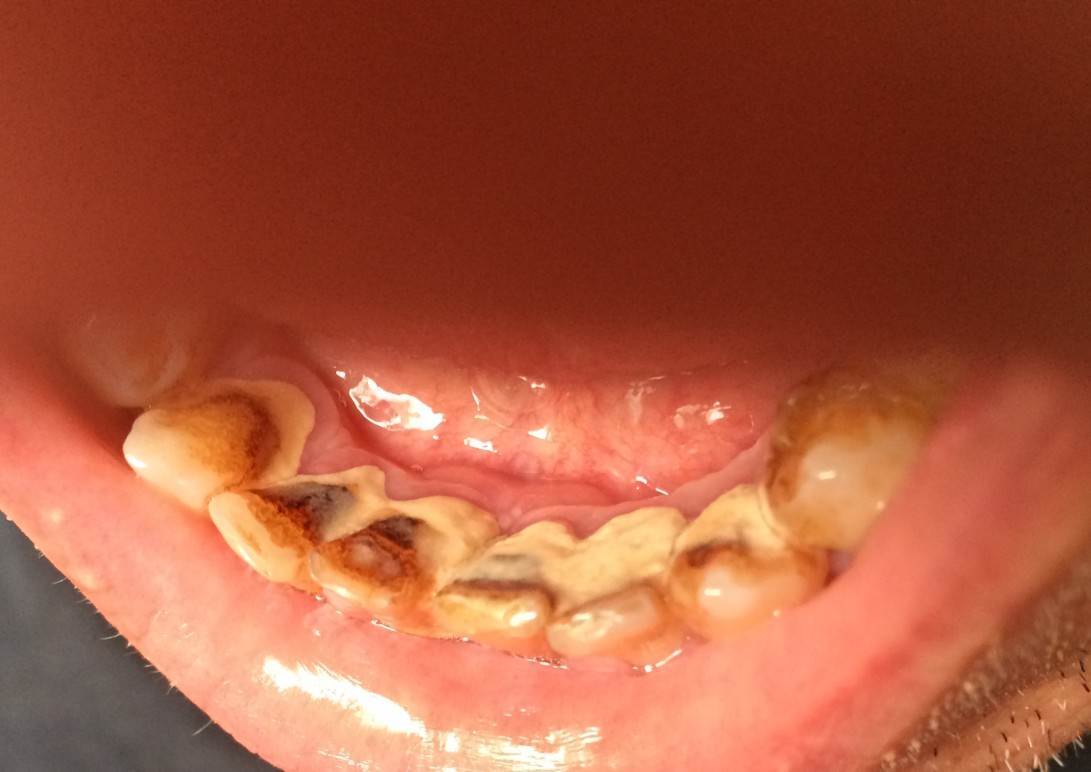

Sergey-010101 Опубликовано 5 октября, 2025 Поделиться Опубликовано 5 октября, 2025 (изменено) Здравствуйте. У меня на нескольких передних зубах большие камни, рецессия десны, на миллиметров 5-6 камень опускается спереди и сзади зуба. В одной стоматологии предложили чистку ручными инструментами. В другой аппаратом Вектор. Что являет более безопасным для чистки камней на корнях? Какой вариант выбрать? Вектор вроде ультразвук использует. А пишут что ультразвуком камни на корнях вредно чистить. Есть ли у Вектора какие то варианты? Насадки? Если выбрать этот способ есть моменты которые нужно уточнить? Обратить более подробное внимание. Изменено 5 октября, 2025 пользователем Sergey-010101 Ссылка на комментарий

Sergey-010101 Опубликовано 5 октября, 2025 Автор Поделиться Опубликовано 5 октября, 2025 И что делать если будут шататься потом, чтобы сохранить? Как нарастить десну кость? Немного есть мнения что есть риск потери. Но в целом несколько врачей сказали что могут даже не шататься. Убыль кости есть на 2-3 мм в некоторых местах, но корень более чем на половину в кости. Ссылка на комментарий